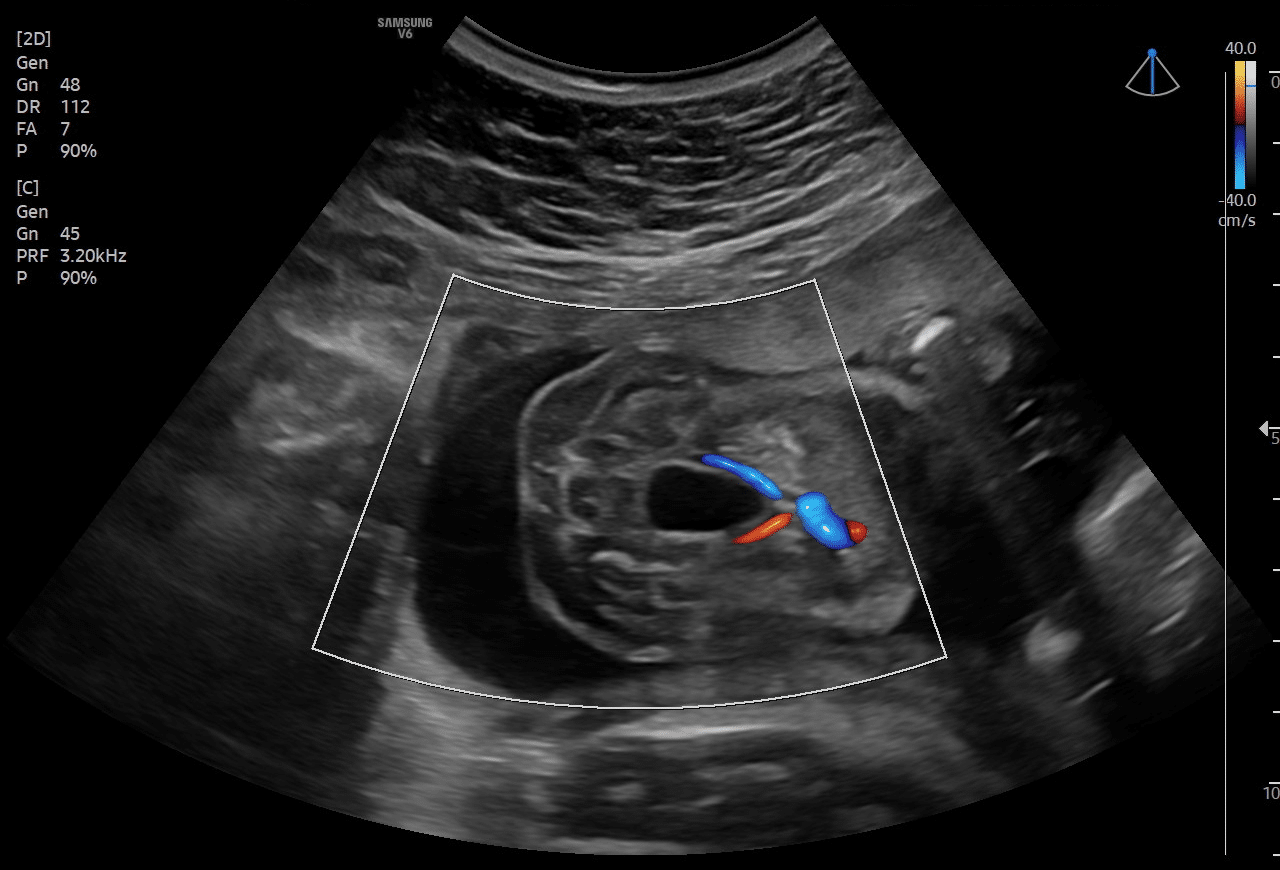

Valores de Referência para o Tamanho da Bexiga Fetal no Segundo e Terceiro Trimestres

As tabelas aqui descritas são denominadas de tabelas de valores de REFERÊNCIA. Valores acima ou abaixo dos limites esperados